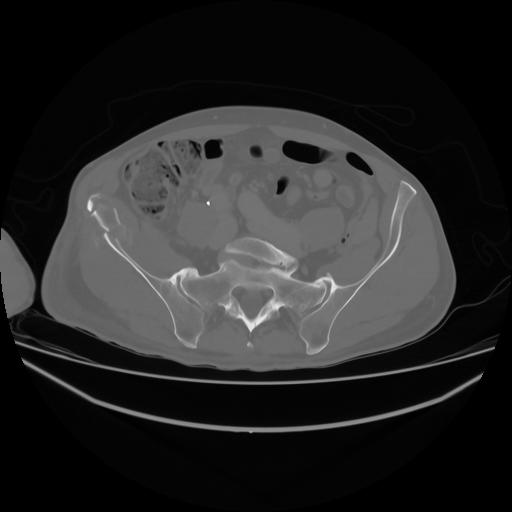

4 CUERPO,CE,Axial,3.0,CUERPO,,